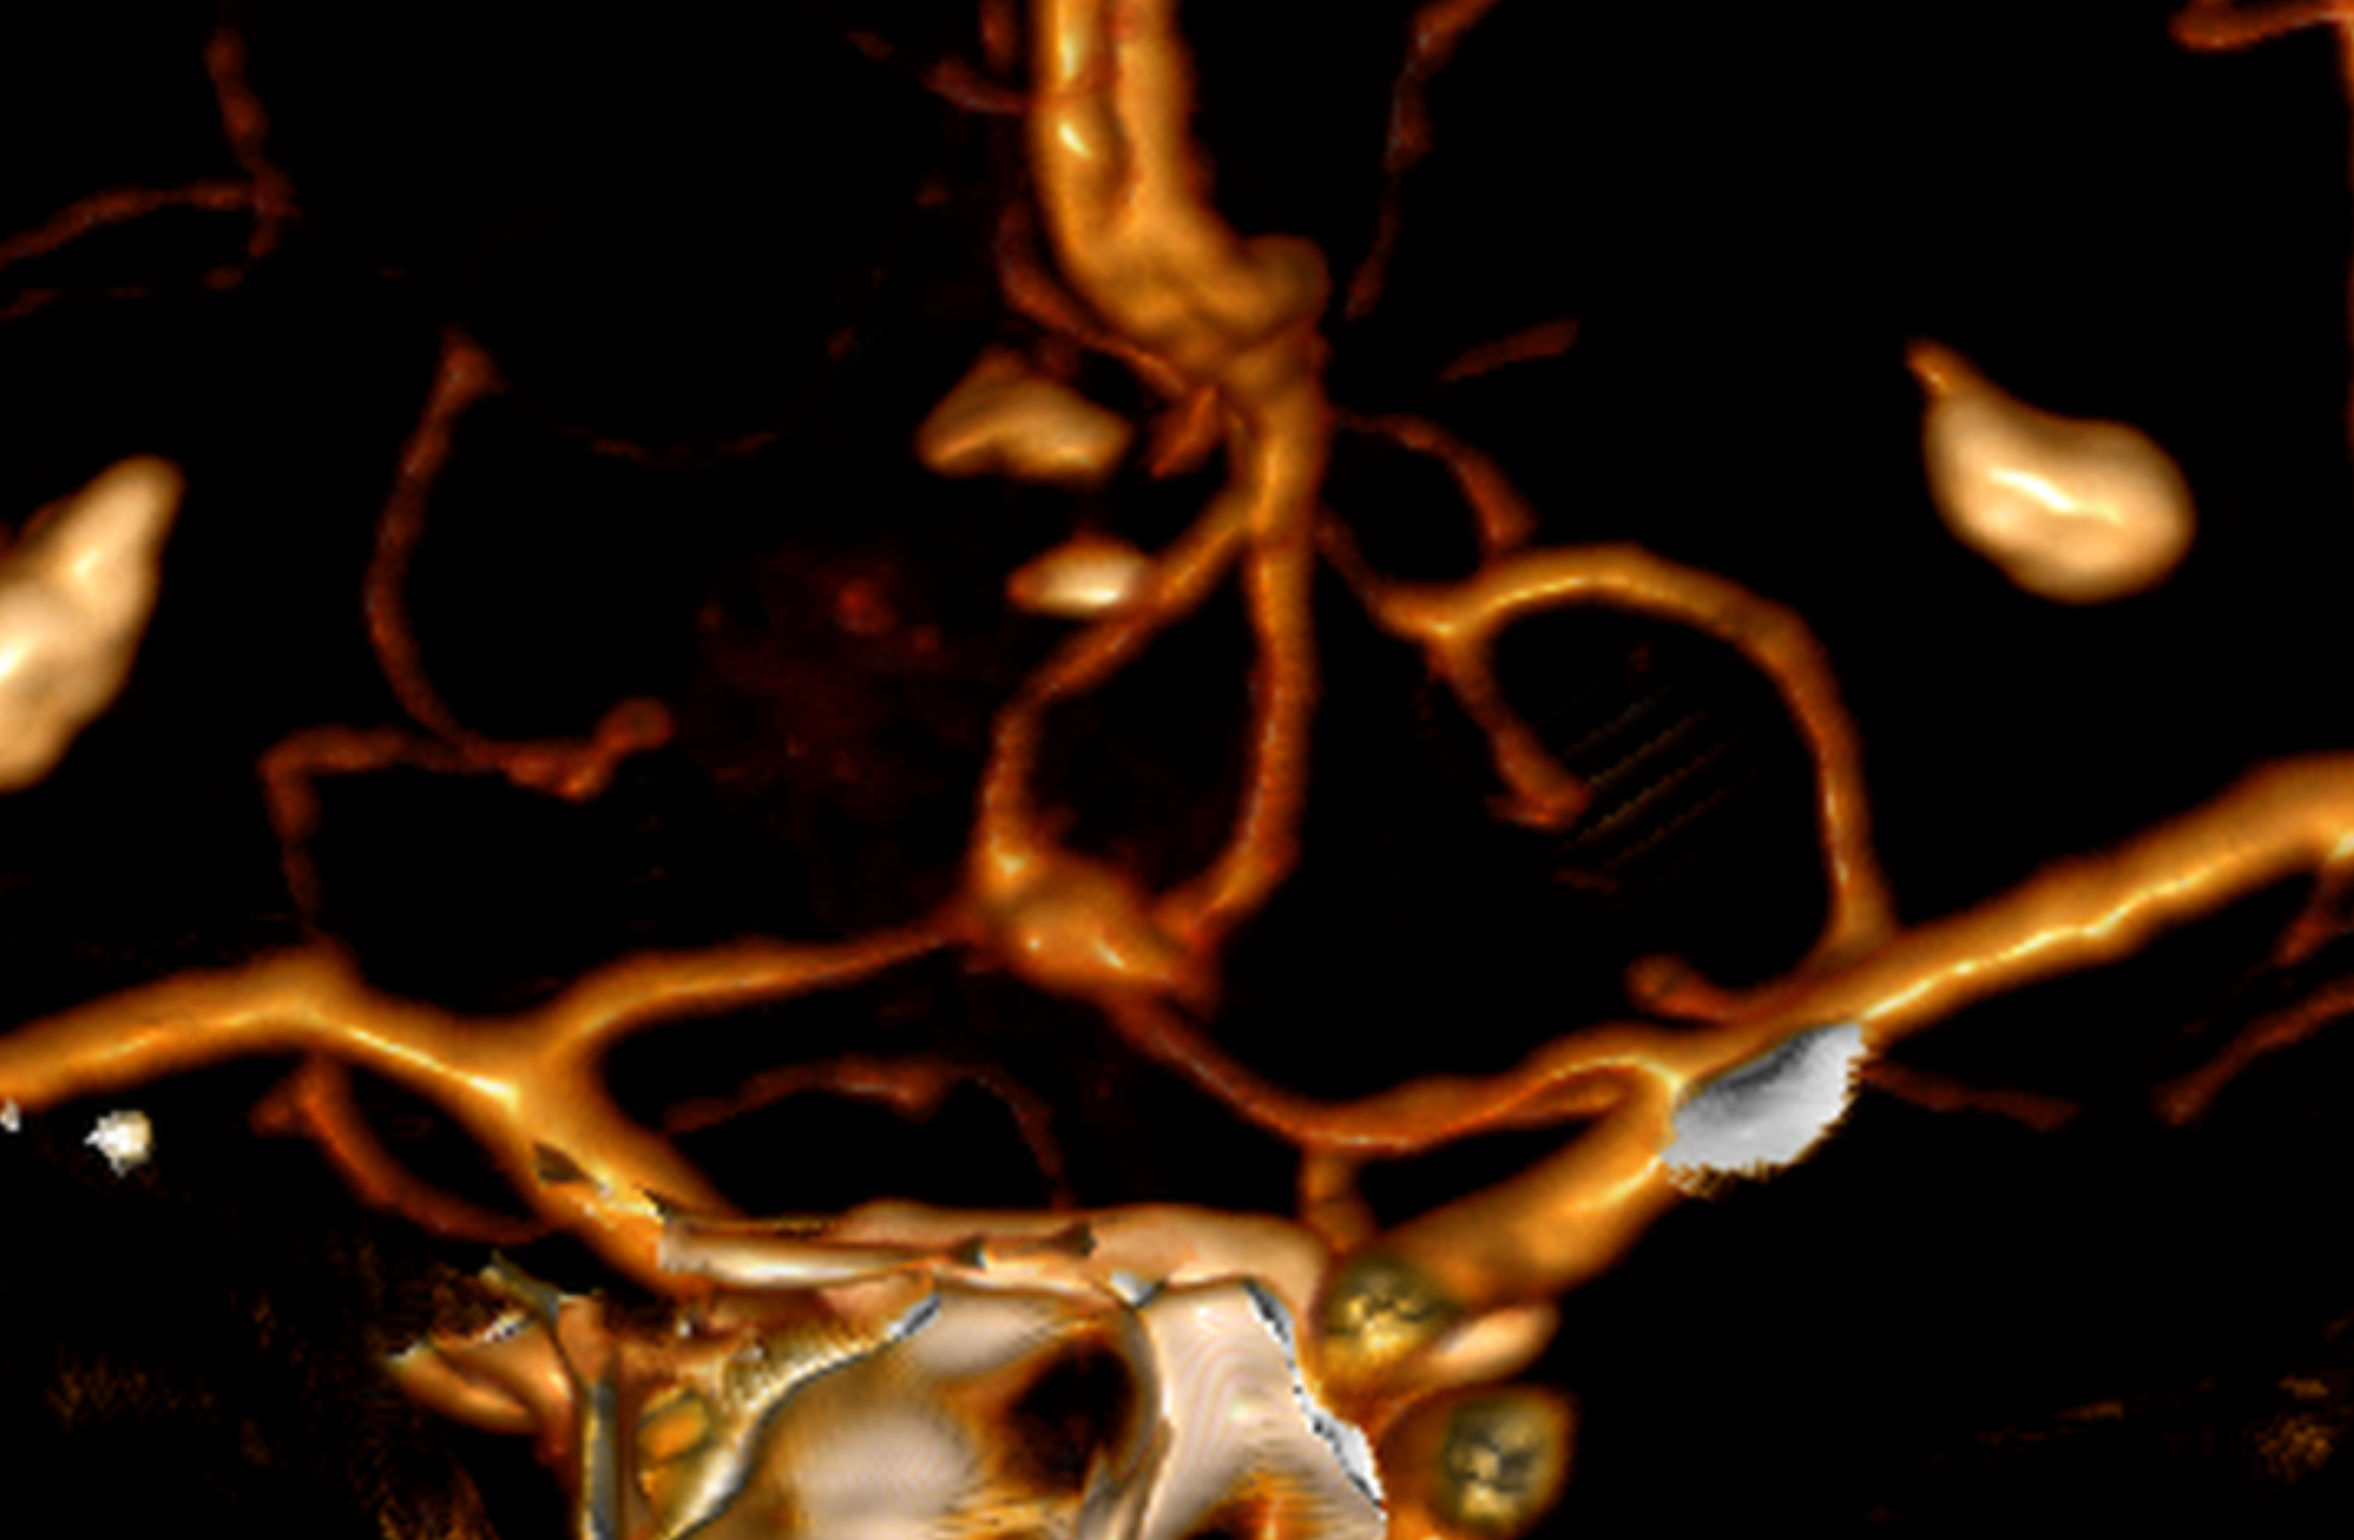

The typical bleeding pattern is seen after aneurysm rupture. The shape and location of the aneurysm can predict its behavior and also determine which treatment is preferred. Alternatively, if the aneurysm has a low risk of rupture or a high surgical risk, we may choose to surveil it with serial imaging. The intervention is designed to block the blood flow into the aneurysm, therefore eliminating the risk of hemorrhage. It can be performed endovascularly – by filling the aneurysm from within (“endovascular coiling”), or by open microsurgical techniques (“clipping”).

Several imaging modalities can be used to define the AVM. Computed Tomography (CT) and its variant Angiotomography provide information on the location and static vascular anatomy, including the vessels supplying and draining the AVM. Magnetic resonance not only tells us where in the brain the AVM is located, it also helps to measure risk and surgical approaches and provides information on previous hemorrhages. Cerebral angiography provides detailed dynamic information on flow patterns and venous drainage. Although it is the most sensitive and powerful test, it is also technically more “invasive” and entails a very small risk of stroke.

3D brain angiography showing an aneurysm